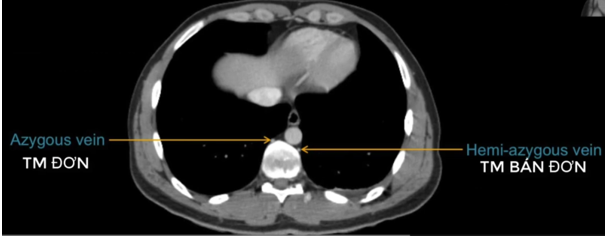

TM gan ở đâu? TM chủ dưới ? ĐM chủ?